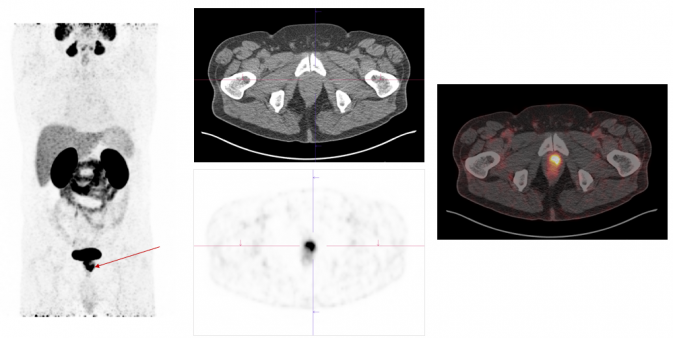

Ga-68-PSMA

Ga-68-PSMA-PET is a nuclear medicine procedure that can be used to image prostate cancer. .

Exemplary case study on PSMA-PET/CT diagnostics: